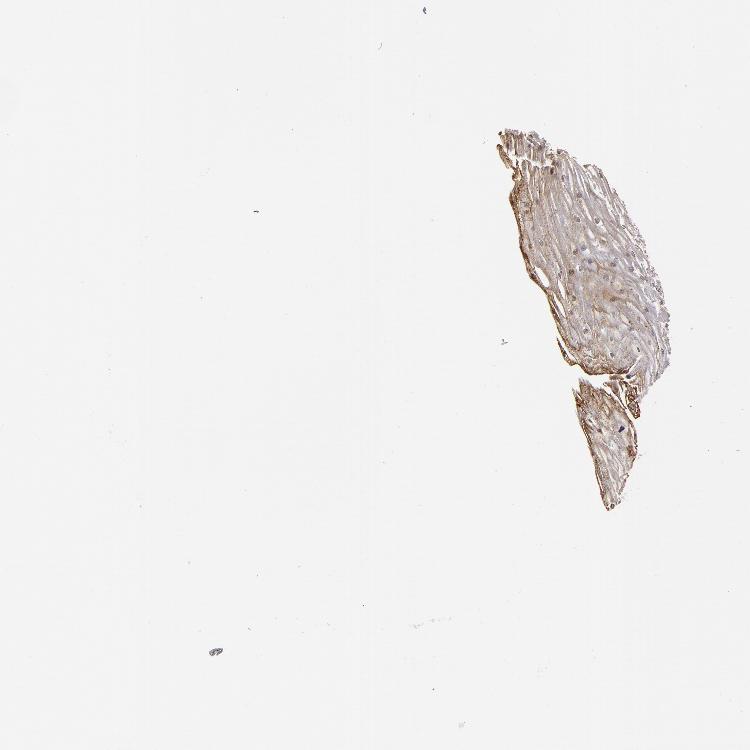

ESOPHAGUS - Antibody stainingi

Antibody staining in the annotated cell types in the current human tissue is reported as not detected, low, medium, or high, based on conventional immunohistochemistry profiling in selected tissues. This score is based on the combination of the staining intensity and fraction of stained cells.

Each image is clickable and will lead to virtual microscopy that enables deeper exploration of all samples and also displays staining intensity scores, fraction scores and subcellular localization as well as patient and tissue information for each sample.

Antibody HPA001538Antibody CAB008632

Squamous epithelial cells MediumMedium